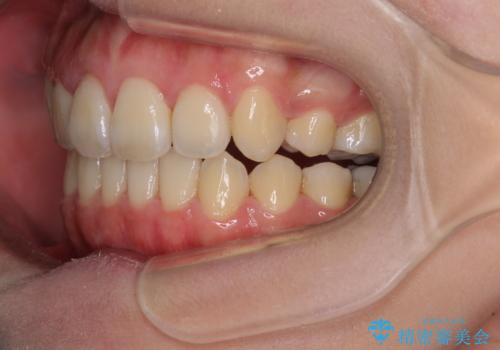

- 八重歯と叢生を気にして来院された患者様です。

上下の前歯が非接触であり、叢生や八重歯が顕著であったため、上顎左右第一小臼歯2本を抜歯して排列することとしました。

抜歯により移動量が多くなるため、ワイヤーや補助装置を活用し、その後インビザラインによる矯正治療を行うこととしました。

元々奥歯に負担のかかる咬み合わせですり減っていたため、仕上がった歯並びでも奥歯が咬んでいないように見えましたが、実際にはしっかりと咬合しており、患者様本人も咬んだ感触に違和感はないとのことでした。